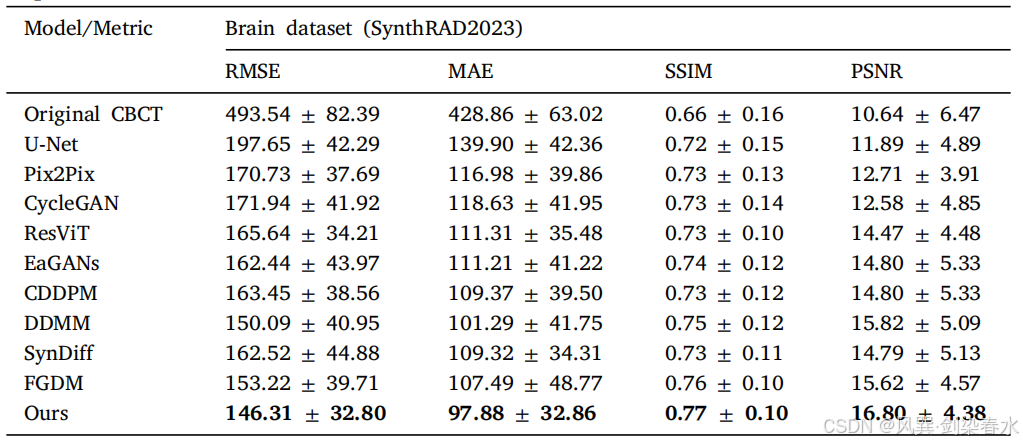

Table 3 | 头部测试数据集的实验结果:

Figure 5 | 头部测试数据集可视化:第二行和第四行显示了红色虚线框标记的放大区域,定量结果位于预测图像底部,CBCT 的显示窗口范围为 [−1000,340] HU,而 CT 和 sCT 的显示窗口则为 [−160,240] HU;